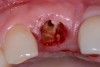

Fig 10. The tooth was extracted; the socket debrided and degranulated; and ridge preservation was performed with FDBA/rhPDGF and an absorbable membrane.

Figure 10

The tooth was extracted, and magnification was used while debriding and degranulating the extraction socket. The site was irrigated with a significant amount of sterile water from 10-mL syringes, and the water pressure helped with debridement. Spoon and #4 Gracey curettes were used.

Once degranulated and debrided, the growth factor matrix (eg, freeze-dried bone allograft that was presoaked in rh-PDGF-BB for about 10 minutes) was condensed into the site. The site was then covered with a collagen membrane and sutured.

After healing, the site was evaluated and a high frenum attachment was observed (Figure 10). A frenectomy was performed prior to implant placement, along with a connective tissue graft to thicken the soft tissues.